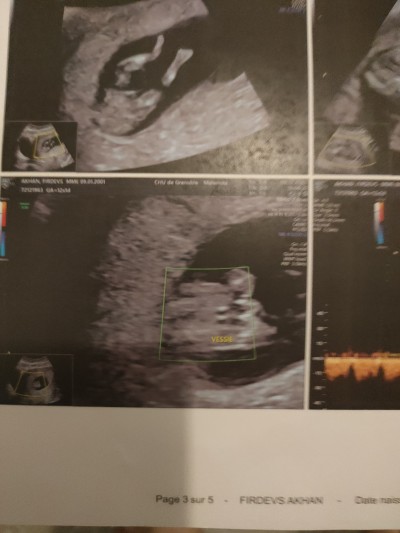

Kızlar bugün doktara gitim cinsiyet tahmini yaparmısınız doktor birşey söylemedi çok merak ediyorum

Gebelik haftası 12+1

neden tahmin de bulunmadı acaba bacak arası boş küçük çıkıntı var oda içe doğru yani kiz bence  haftanız küçük diye demedi demek ki birsey

Ben erkeğe benzettim. Sağlıkla kucağınıza alın.